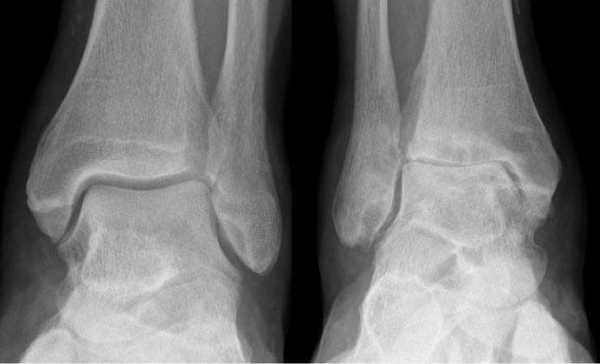

Артроз левого сустава. Суставная щель очень мала.

- вторичный (посттравматический) и первичный артроз 3-4 ст.;